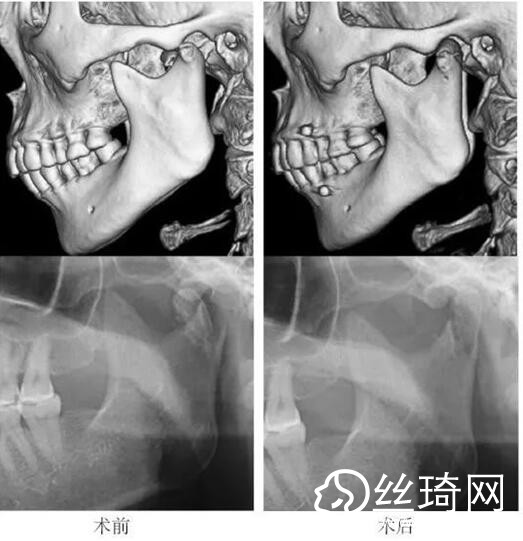

在106側(cè)中,髁突高位矢狀骨折46側(cè),中位髁頸骨折26側(cè),低位髁頸下骨折34側(cè)。髁突高位矢狀骨折及中位髁頸骨折均經(jīng)耳屏前徑路復(fù)位;34側(cè)低位髁頸下骨折中,經(jīng)耳屏前徑路復(fù)位13側(cè),頜下徑路復(fù)位19側(cè),頜后徑路復(fù)位1側(cè),穿腮腺徑路復(fù)位1側(cè)。髁突高位矢狀骨折復(fù)位后以1~2枚可吸收長螺釘固定(圖1)[3],采用的可吸收內(nèi)固定系統(tǒng)為BioSorb(ConMed Linvatec,芬蘭)、Inion OTPS(Inion,芬蘭);規(guī)格:直徑2 mm,長度15~20 mm。中位髁頸骨折及低位髁頸下骨折多以2塊可吸收板固定(圖2)[3],個別病例以1塊或3塊可吸收板固定,采用的可吸收內(nèi)固定系統(tǒng)為BioSorb(ConMed Linvatec,芬蘭)、Grand Fix(Gunze,日本)、Inion OTPS(Inion,芬蘭);規(guī)格:直4孔板,孔徑 mm或2.5 mm,長度21~35 mm,螺釘直徑 mm或2.5 mm,長度7~10 mm。可吸收釘板的手術(shù)操作采用專用器械工具盒,并遵照廠家操作指引進(jìn)行。

82例髁突骨折患者,術(shù)后隨訪6個月至3年,平均年。所有患者術(shù)后未訴明X不適,面型基本對稱,面部肌肉運(yùn)動正常,咬合對位良好,開口度~4.2 cm,平均(±)cm。3例患者開口型輕度偏斜,均為髁突高位骨折,其中2例為粉碎性骨折行骨折碎片摘除,1例為矢狀骨折,以可吸收螺釘固定后,創(chuàng)口感染,隨后行局部清創(chuàng)并取出髁突骨折片及可吸收螺釘,創(chuàng)口愈合良好。96側(cè)髁突骨折中,2例髁頸下骨折術(shù)后復(fù)查CT顯示輕度移位,但患者無功能障礙,持續(xù)觀察,未做特殊處理。其他患者未見明X排斥反應(yīng)及并發(fā)癥。

本組病例中,絕大多數(shù)髁頸、髁頸下骨折均經(jīng)耳屏前或頜下切口進(jìn)行復(fù)位固定,均獲得了良好的復(fù)位固定性及療。有2例患者輕度移位,可能與過早承重及可吸收材料的強(qiáng)度較弱有關(guān)。